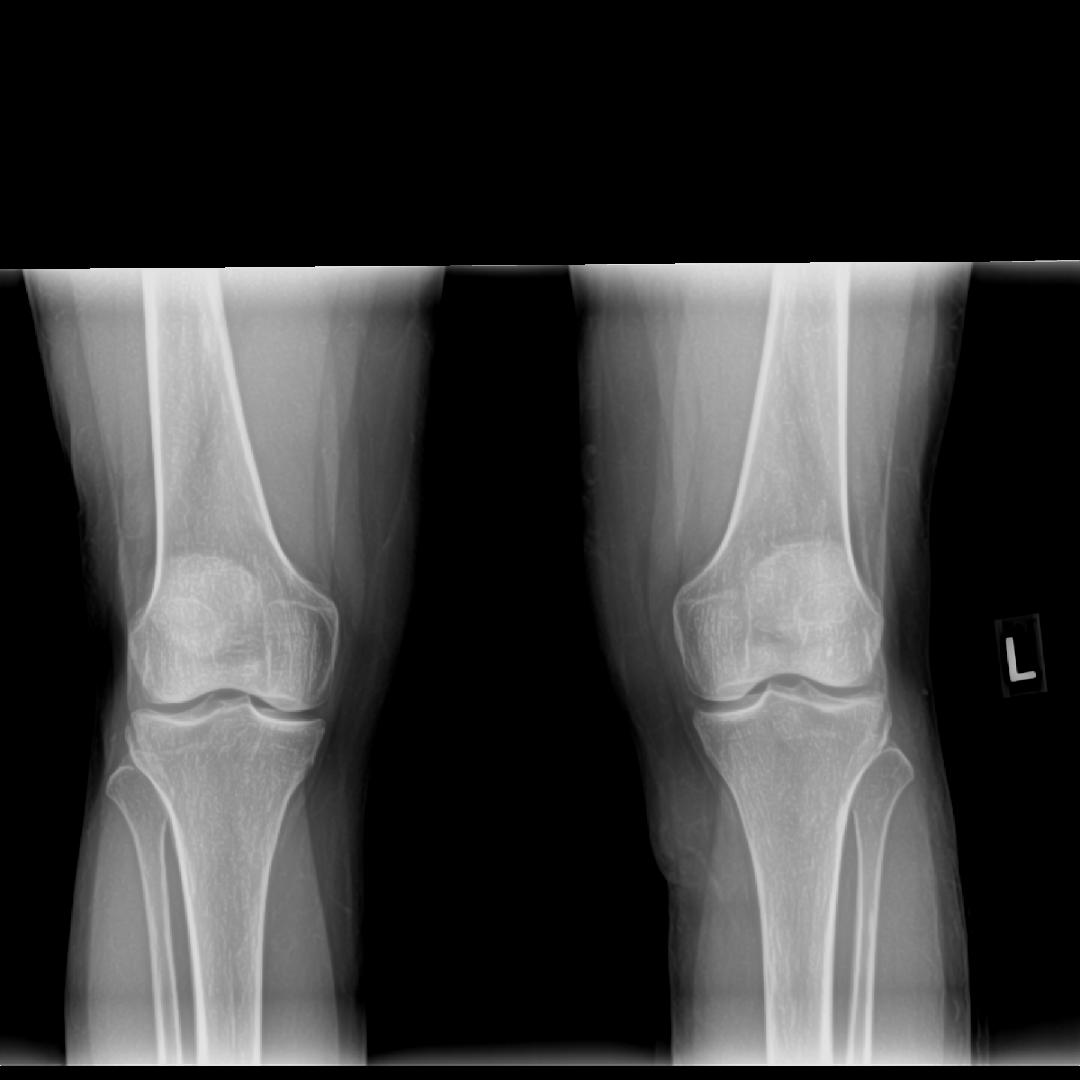

These following two x-rays taken 4-17-13 by Dr. Scott Sheldon, Dwyer Chiropractic, Clarkston, WA:

His interpretation of x-rays: “There is a slight wedge on the lateral aspect of her left knee in the joint space. The left tibia shows anterior rotation on the the AP view. The left fibula has mild lateral displacement. There are no remarkable findings of degeneration. There are no remarkable findings on the right knee.”

Quoting from my office chart note the pertinent findings with the bold type my emphasis: “Musculoskeletal examination demonstrates her to walk about the clinic with assistive devices. She has a Coban wrap involving her left lower extremity from the knee to the ankle. Once removed she does have mild swelling overlying the lateral aspect of the left proximal leg region just below the level of the lateral joint line. There is a trace amount of swelling involving the left ankle….She is tender to palpation overlying the anterior tib/fib ligament, the distal tib/fib syndesmosis, the ATFL and the CCFL….Dorsiflexion and external rotation stress test elicits minimal pain at the ankle but more pain along the mid syndesmotic region. Cotton squeeze test is negative distally but is positive proximally….Examination of the left proximal tib/fib articulation demonstrates evidence of marked increase mobility of the proximal fibula in relationship to the tibia. She is noted to have a posterior and inferior instability pattern. This instability becomes worse with the leg externally rotated and it tightens with the leg internally rotated….X-rays from an outside facility reviewed about the left knee including AP and lateral demonstrates no gross evidence of arthritis changes present. The overall articulation of the proximal tib/fib joint appears to be well aligned….X-rays obtained today of her left ankle in our facility, AP, mortis and lateral views demonstrates the syndesmosis and ankle mortis to be well aligned. There are no signs of fractures or avulsion injuries noted….Outside MRI of left knee is also reviewed, which demonstrates no gross evidence of collateral or cruciate liagment tear or laxity or involvement. The meniscus appears to be intact. Minimal arthritic changes are present. There is mild increased fluid accumulation and swelling around the proximal tib/fib articulation.”